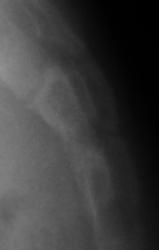

Ребенок направлен хирургом на рентгенографию крестца и копчика, Накануне ребенок упал. Приводится только боковая рентгенограмма, так как рентгенограмма, выполненная в прямой проекции не информативна.

Вопрос. Есть перелом или нет перелома?

Перелома нет

Уважаемый Валентин Львович! Наличия костно-травматических изменений со стороны объекта исследования не выявлено. Кстати, у меня редко получаются такие красивые рентгенограммы крестца и копчика.